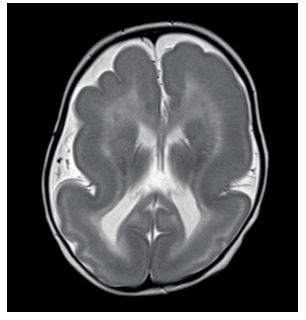

Lisencefalia (“Cérebro Liso”)

Falha grave na migração. O córtex fica espesso e com poucas ou nenhuma circunvolução.

- Agiria: Ausência total de giros.

- Paquigiria: Giros poucos, largos e rasos.

- Genética: Gene LIS1 (PAFAH1B1) em 60% dos casos.